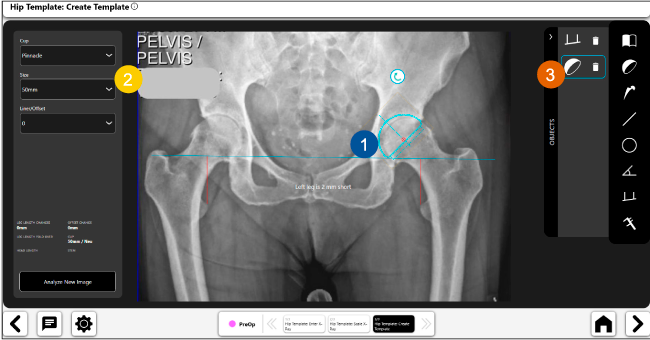

Planeación preoperatoria mediante la creación de plantillas digitales para reemplazo de cadera y análisis intraoperatorio

Disponibilidad de plantillas digitales de cadera.

Expediente histórico y personalizado, optimiza la planeación con el calendario de casos realizados en Velys TM y utiliza los íconos interactivos para una rápida revisión.

Espacio colaborativo: puede compartir los casos entre cirujanos y sus equipos mediante la funcionalidad de intercambio de información.

Beneficios de la planeación preoperatoria con Velys Hip Navigation ™